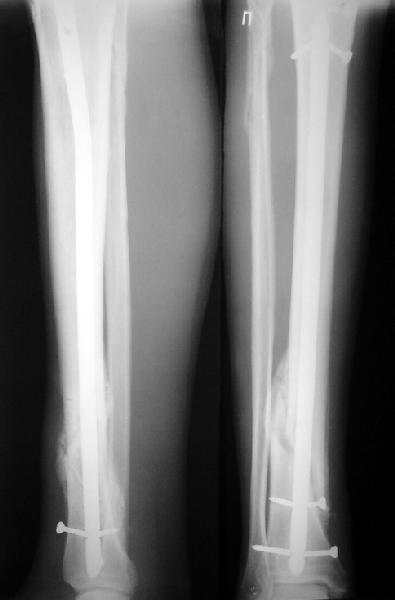

Ok. А также и следующий, в 3 месяца.

Это наглядная демонстрация возможности ранней полной нагрузки при нестабильном по оси повреждении, причем не в самых благоприятных механических условиях - при плохом сопоставлении, со слабым фиксатором.

Сверху - один статический винт, а снизу - три. Что раньше сломается? Конечно, он потом и нижние сломал, и Вы правы, если бы верхний динамичесий винт уже уперся бы в нижний край отверстия, будь гвоздь подлинее, перфорировал бы сустав как пить дать.

Как я уже говорил, мы сделали выводы из этого и других подобных случаев. Очевидно, решений проблемы два - либо уменьшить нагрузку, либо увеличить прочность фиксатора. Первое решение работает не со всеми больными, так что пошли по второму пути - мы больше не используем гвозди с запирающими винтами диаметром 4 мм.